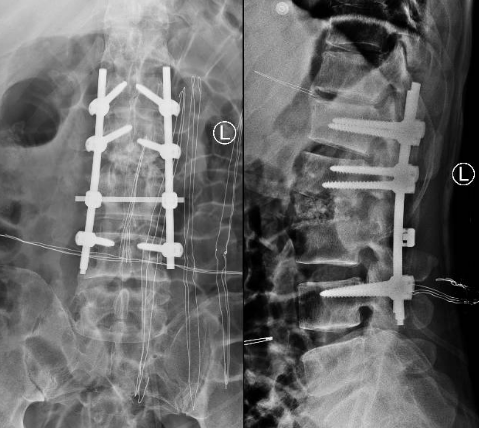

术后X线片

患者出院后感腰部疼痛持续加重,到飞禽走兽攻略站 门诊就诊,以“腰椎感染”收住入院。患者发病后腰椎CT及MRI均提示腰2-3椎间隙变窄,椎板破坏,综合以上资料诊断”腰椎结核”。入院后经口服四联抗结核药物治疗3周,患者自觉腰部疼痛减轻,午后无发热及盗汗后,在全麻下行颈后路病灶清除、椎间植骨、椎弓根钉棒系统内固定术。手术顺利,术后继续抗结核治疗。患者恢复顺利,术后1周下床活动,无特殊不适。术后2周拆线、出院,院外继续口服抗结核药物治疗,定期门诊复查。